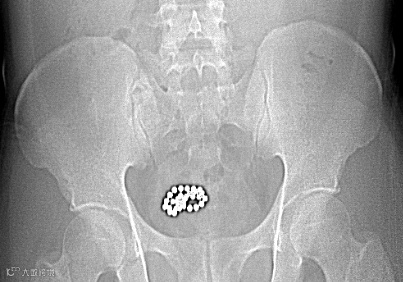

近日,北海市中医医院泌尿外科接诊了一例特殊病例:一名28岁青年男性因反复尿频、尿急、尿血,来院就诊后发现,其尿道内竟藏有31颗磁力珠!

经询问,患者因一时好奇将磁力珠塞入尿道,未及时取出,导致珠子滞留体内引发感染。我院泌尿外科团队迅速制定方案,通过麻醉及手术,成功将31颗磁力珠完整取出,患者术后恢复良好。